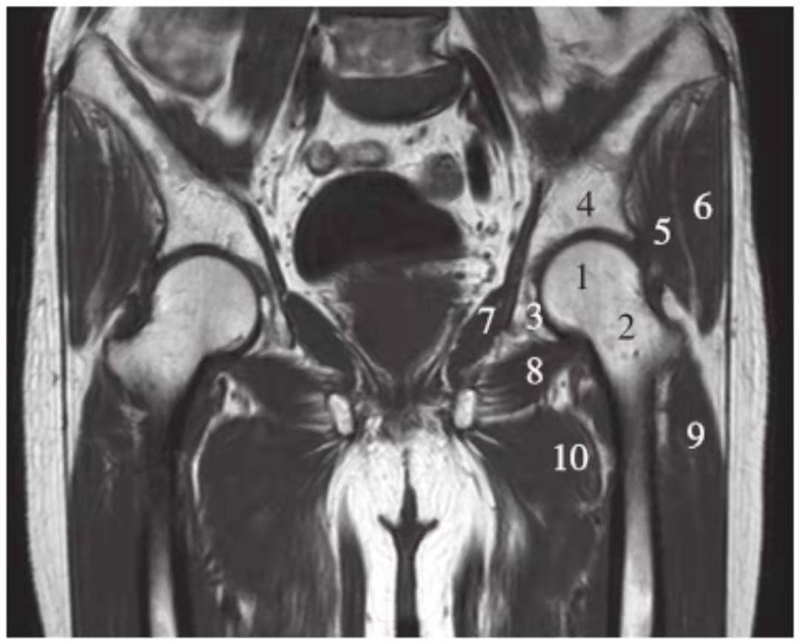

冠状位

正常髋关节经股骨头中心层面T1WI像

1.股骨头;2.股骨颈;3.髋臼窝内脂肪;4.髂骨;5.臀小肌;6.臀中肌;7.闭孔内肌;8.闭孔外肌;9.股外侧肌;10.股内侧肌